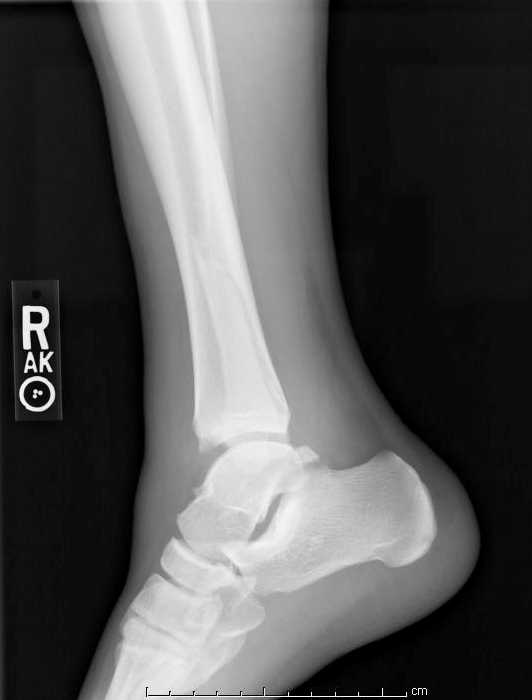

In addition to a spiral fracture of the distal diaphysis of the fibula, the patient’s imaging is concerning for a high ankle sprain given the medial displacement of the tibia, lateral displacement of the fibula, and increased tibiofibular clear space.

Below are the patient’s initial ankle radiographs. Based on the Weber ankle fracture classification, what would be the likely course of management for this patient?

The Danis-Weber classification system for ankle fractures has three major classifications for fibular fracture: Type A, B, and C. In general, the more proximal the fracture the greater risk of disruption of the syndesmotic ligaments, and thus greater associated instability.[6] Type A refers to a lateral malleolar avulsion fracture below the level of the talar dome. Type B refers to an oblique or spiral fracture of the fibula at or near the level of the syndesmosis. Evidence suggests that Type A and Type B fractures unimalleolar fractures have similar outcomes, showing lower rates of complications compared to Type C. However, other important factors inversely correlated with prognosis include the number of malleoli fractured and the age of patients.[7]

This ankle fracture would specifically be a Weber type C ankle fracture. Weber type C ankle fractures are above the level of the ankle joint with tibiofibular syndesmosis disruption and associated medial injury.[6] It is important to note that Weber type C ankle fractures may arise as proximally as the fibular neck, and thus full evaluation of the fibula (on both physical exam and on radiographs) is necessary. This fracture is unstable and usually requires referral for an orthopedic consult for open reduction and internal fixation.

Figure 3. Lateral view X-ray of ankle demonstrating a spiral fracture of the fibula above the level of the ankle joint.